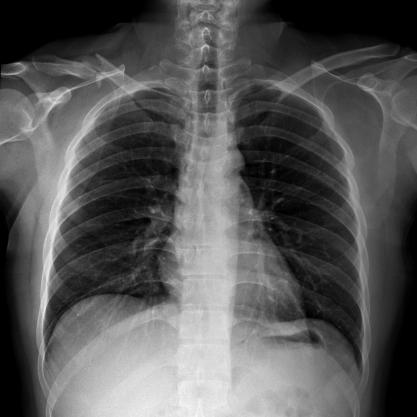

多功能动态平板DR,采用U型臂结构,具有静态DR摄影、数字透视、数字造影和可视化摄影的功能。

满足不同身高的受检者快速地进行胸片的静态及动态检查,适合大规模体检。

SID可拉伸至1.8米,满足标准胸片、职业性尘肺病检查等特殊需求。